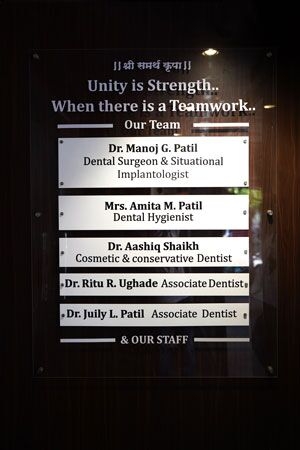

It’s a 500 square feet spacious dental setup located in a prime location in Kalyan west. The Clinic has in house OPG machine for early diagnosis and latest sterilization equipment. Our team is very well trained for handling all types of dental treatments and emergencies.

We offer all types of dental treatments at our dental clinic including basic and advanced treatments like full mouth dental implants.